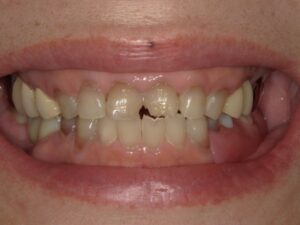

こちらがノンクラスプデンチャーの写真になります。

適合が問題ないことや歯茎とぶつかっている部位がないことなど念入りに確認し、噛み合わせも細かく調整を行いセットいたしました。毎日ご自身で着脱を行なってもらいますので、着脱の練習も十分にしてもらいました。

患者様はまず見た目に大変満足されておりました。入れ歯となった際はやはり金属のバネがかかる入れ歯を想像されていたようですが、周囲の人に入れ歯と分からないような入れ歯が入り、とても安心されておりました。最初は違和感や固いものを噛んだ時の痛みはあるようでしたが、徐々に気にならなくなったとのことです。

こちらの写真を見て、入れ歯をしているなと気がつく一般の人はかなり少ないかと思います。